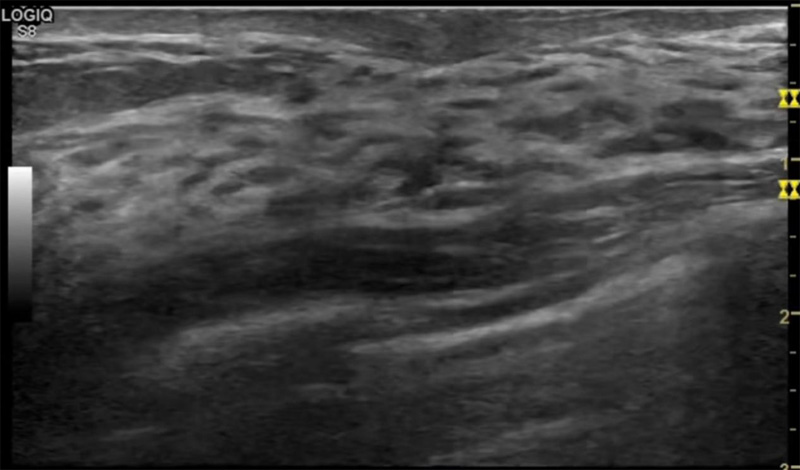

乳房胀痛,触摸疼痛,手摸起来感觉有肿块。这个是什么问题呢?医生诊断一般是乳腺增生。那么在乳腺91香蕉视频APP在线下载网址入口检查后,报告单却显示双乳未见明显占位性病变。乳腺增生是很多女性,特别是育龄期女性都有的经历、到底乳腺增生症状有哪些?会给91香蕉短视频污带来怎样的影响呢?乳腺增生不是肿瘤跟炎症。乳腺组织增生及退行性变跟内分泌功能紊乱有关系。正常的生理改变。还有乳腺病,良性乳腺结构不良等名称。

乳腺增生有什么症状,病因?比较典型的就是乳房疼痛,特别是经前症状比较重,经后就有所缓解。有时候还能碰到乳房硬块。根据经期的变化而变化硬度大小都有变。乳腺在内分泌激素,伴随月经周期有增生问题。内分泌激素代谢失衡,雌激素水平增高,出现乳腺组织增生过度,增生组织不退的情况下,就会有乳腺增生症状。这个不会增加乳腺癌的风险。所以不用紧张的。不过乳腺癌的病人都会有乳腺增生。所以乳腺增长有没症状,都需要进行常规的体检。